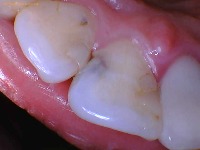

Cavity on top of tooth

Tooth decay that is on top of the tooth is located on the chewing surface of teeth. This surface is called the "occlusal" surface.

The color of this lesion usually starts off as a very light brown but as it progresses, it turns into a darker shade of brown. It can also turn into a black color if it stains very badly. The texture is also soft if you probe it with an instrument.

This type of cavity will also not show up on x-rays like the side tooth cavities. They will only appear on the dental x-ray if they grow to a substantial size but usually when that happens, it involves more than one surface.

What it looks like:

Brown to black in color

May have a hole